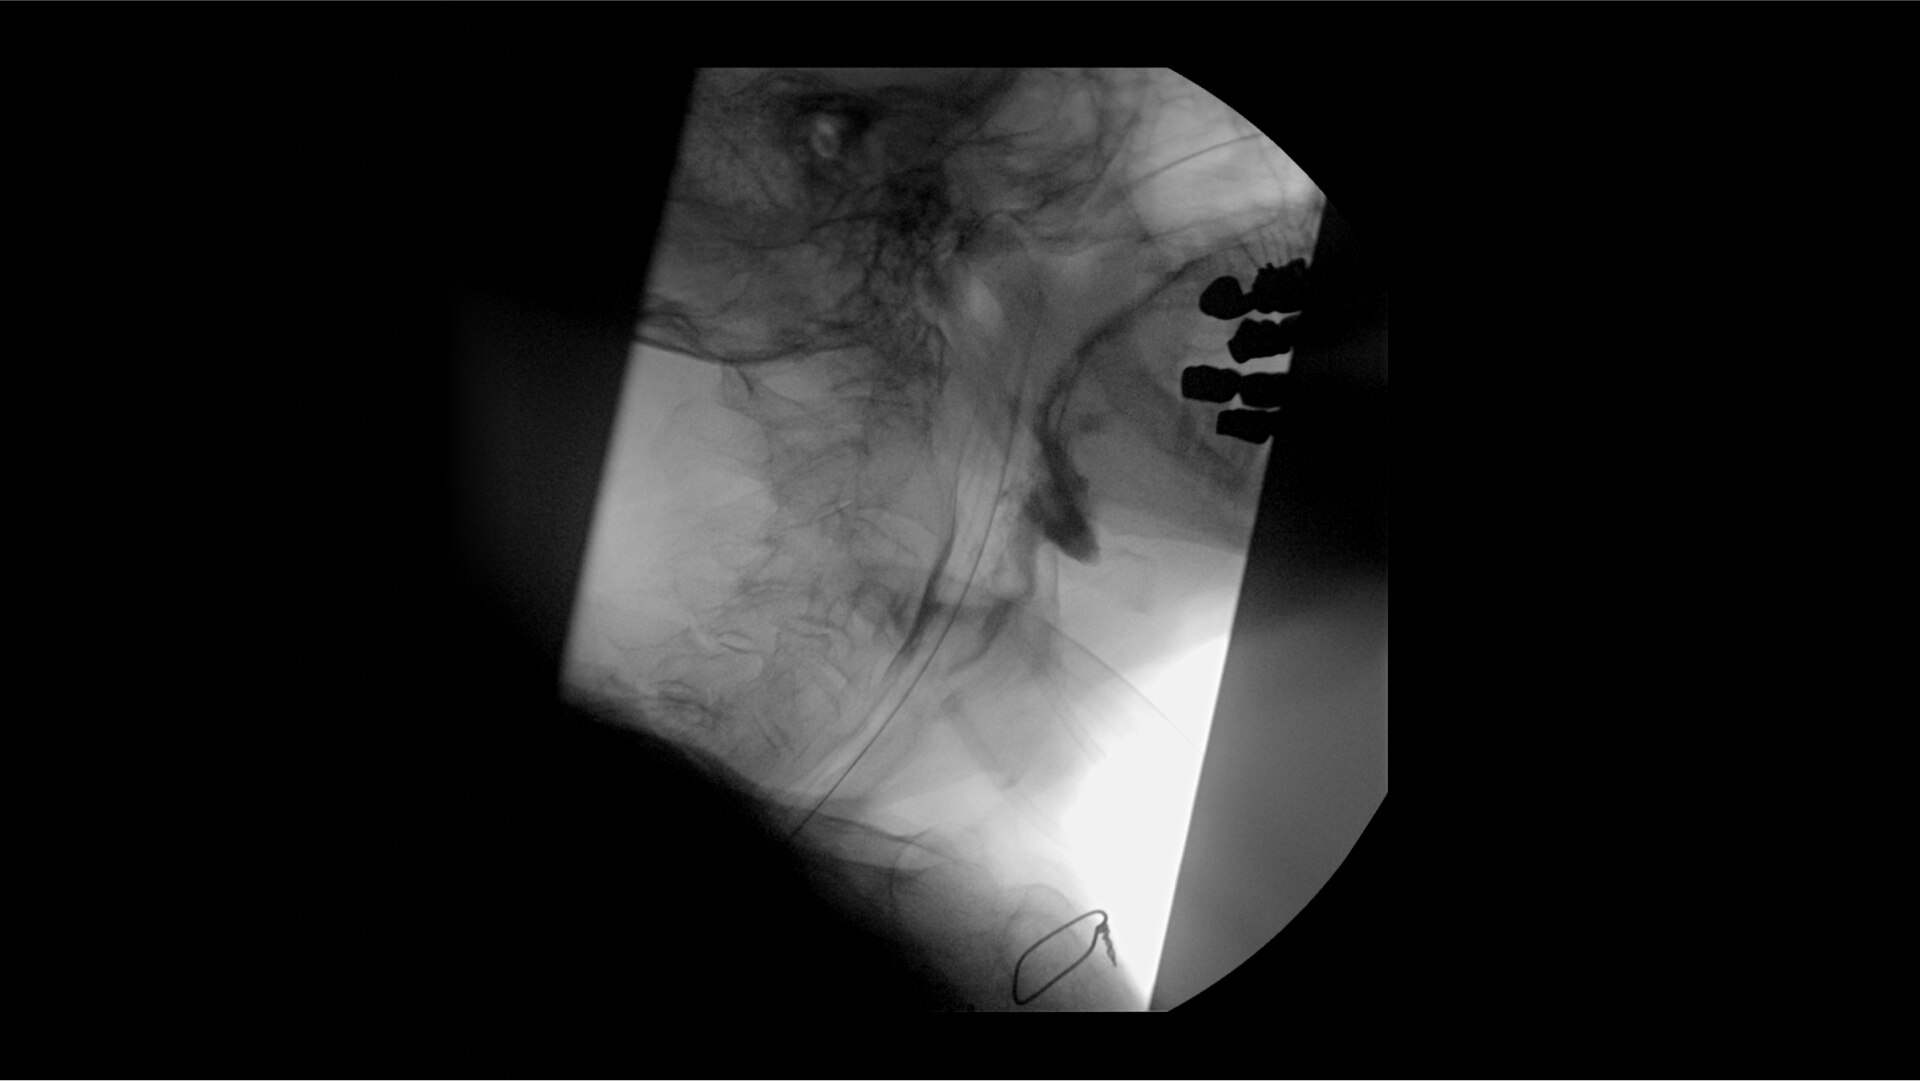

Clearly visualize the GI tract of patients, regardless of size, during a wide range of endoscopic procedures, including ERCP. OEC C-arms offer amazing image quality at low dose and provide enhancements for clear visualization during movement in soft tissue, such as during guidance of low-density drainage tubes or thin biopsy brushes. A large, clear display with comfortable viewing enables effortless workflow.

See detail 1 for 1 from detector to a 4K UHD display for stunning image quality and visualization of low density drainage tubes and thin biopsy brushes.

With OEC Elite CFD, the General HD preset profile optimizes to present high contrast, enhanced edge images to optimally see small detail such as stones in pancreatic duct.

Live Zoom up to 4X during a fluoro or Cine without the additional dose of Mag modes or resulting X-ray tube heat buildup to see guidewires or tubes during procedures.

Capture up to 22% more Field of View by positioning the OEC Elite detector closer to patient anatomy with the OEC low-profile X-ray tube housing compared to mono-block C-arms.